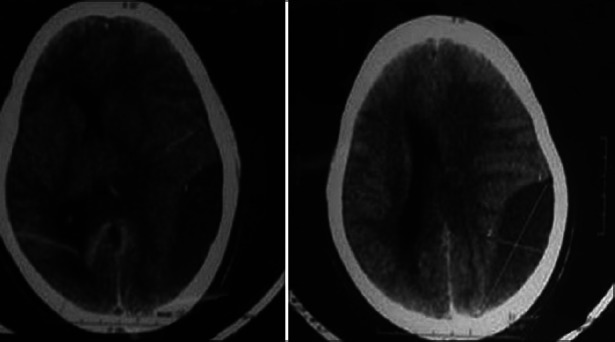

Intracranial hemorrhage is a rare devastating complication of idiopathic thrombocytopenic purpura (ITP), mostly presenting as intraparenchymal or subarachnoid haemorrhage. Isolated chronic subdural haematoma (SDH) is still very rare and the optimal management is unsettled. Spontaneous resolution of chronic SDH in patients with idiopathic thrombocytopenic purpura is possible. We report a case of spontaneous chronic SDH in a patient with ITP with hemiparesis where the haematoma significantly decreased in size with complete resolution of hemiparesis as a result of platelet transfusions and continuing therapy with steroids. Surgical treatment of subdural haematoma with consequent bleeding complications can be avoided in this scenario.